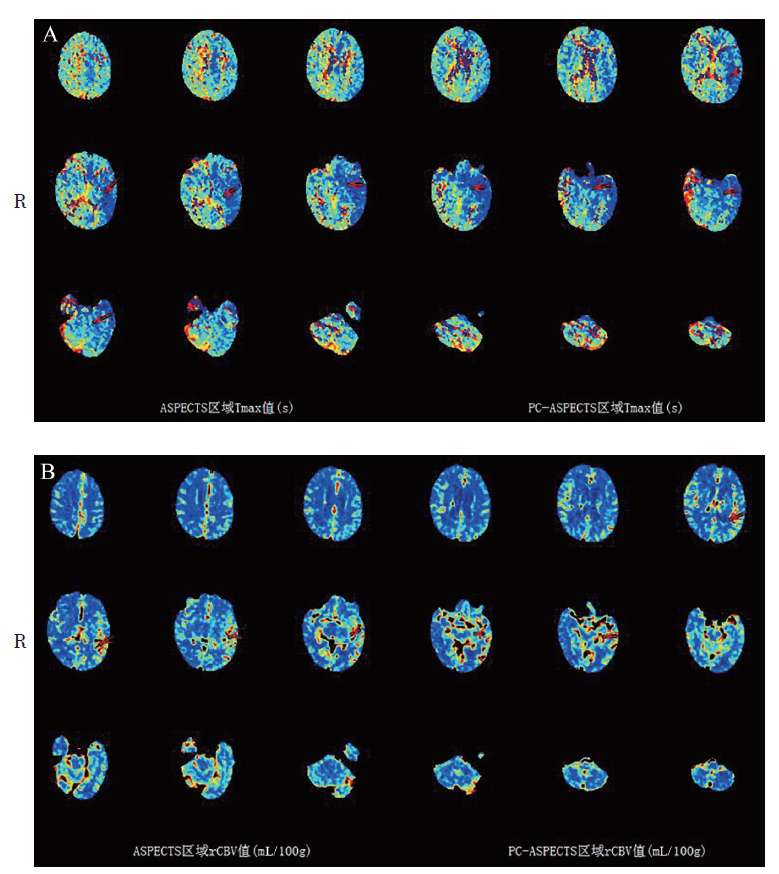

图2 一例HSE患者头颅CTP

注:可见左侧颞叶、豆状核、岛叶、丘脑灌注较右侧增加(红色箭头所示)。